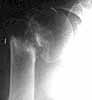

64 yr old gentleman who lives independently. Drinks alcohol daily, chronically. He initially presented 1 month s/p fall complaining of persistent pain in his left shoulder. Radiographs at that time showed a 2-part left prox humerus fracture. Initial treatment with a sling full time.

On follow-up 4 wks later, patient states he wore the sling only 50% of the time. Still has pain in the shoulder. Has gross motion at the fx site on clinical exam. New x-rays attached.

My inclination is to perform ORIF with the Synthes locking prox hum plate with bone graft, but wonder about the amount of bone loss and excavation of the humeral head.